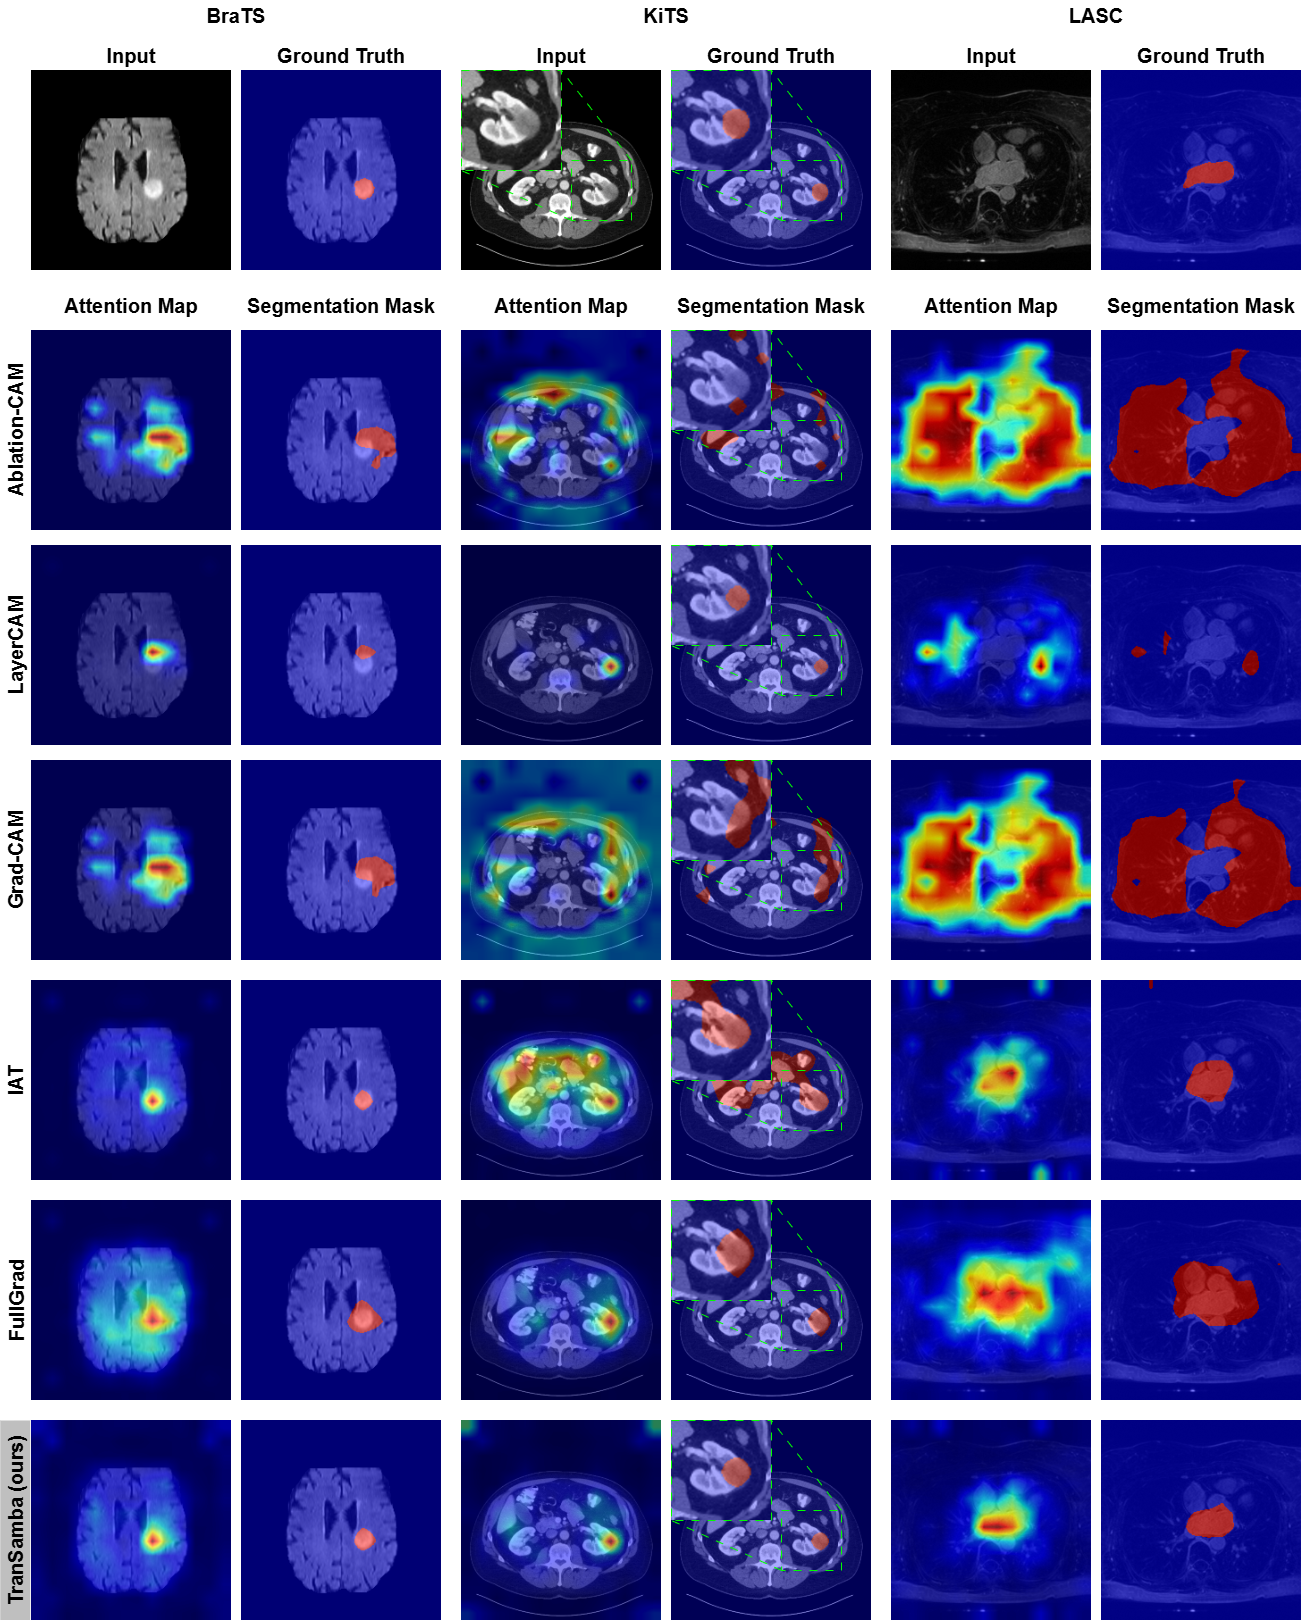

Appendix D Qualitative Comparison with State-of-the-Art

The comprehensive qualitative comparison with SOTA methods is presented in \figurereffig6 and \figurereffig7. In the BraTS case, most methods successfully localize the tumor; exceptions include XGrad-CAM [fu2020axiom], which primarily activates the background, and Eigen-CAM [muhammad2020eigen], which activates the entire brain area. Similarly, in the KiTS case, Eigen-CAM activates the entire body area. Only four methods, Grad-CAM++ [chattopadhay2018grad], LayerCAM [jiang2021layercam], FullGrad [srinivas2019full], and TranSamba, successfully localize the small tumor attached to the left kidney. The LASC case also presents a significant challenge, with only Grad-CAM++, IAT [lyu2024importance], FullGrad, and TranSamba successfully localizing the LA.

fig6

fig7